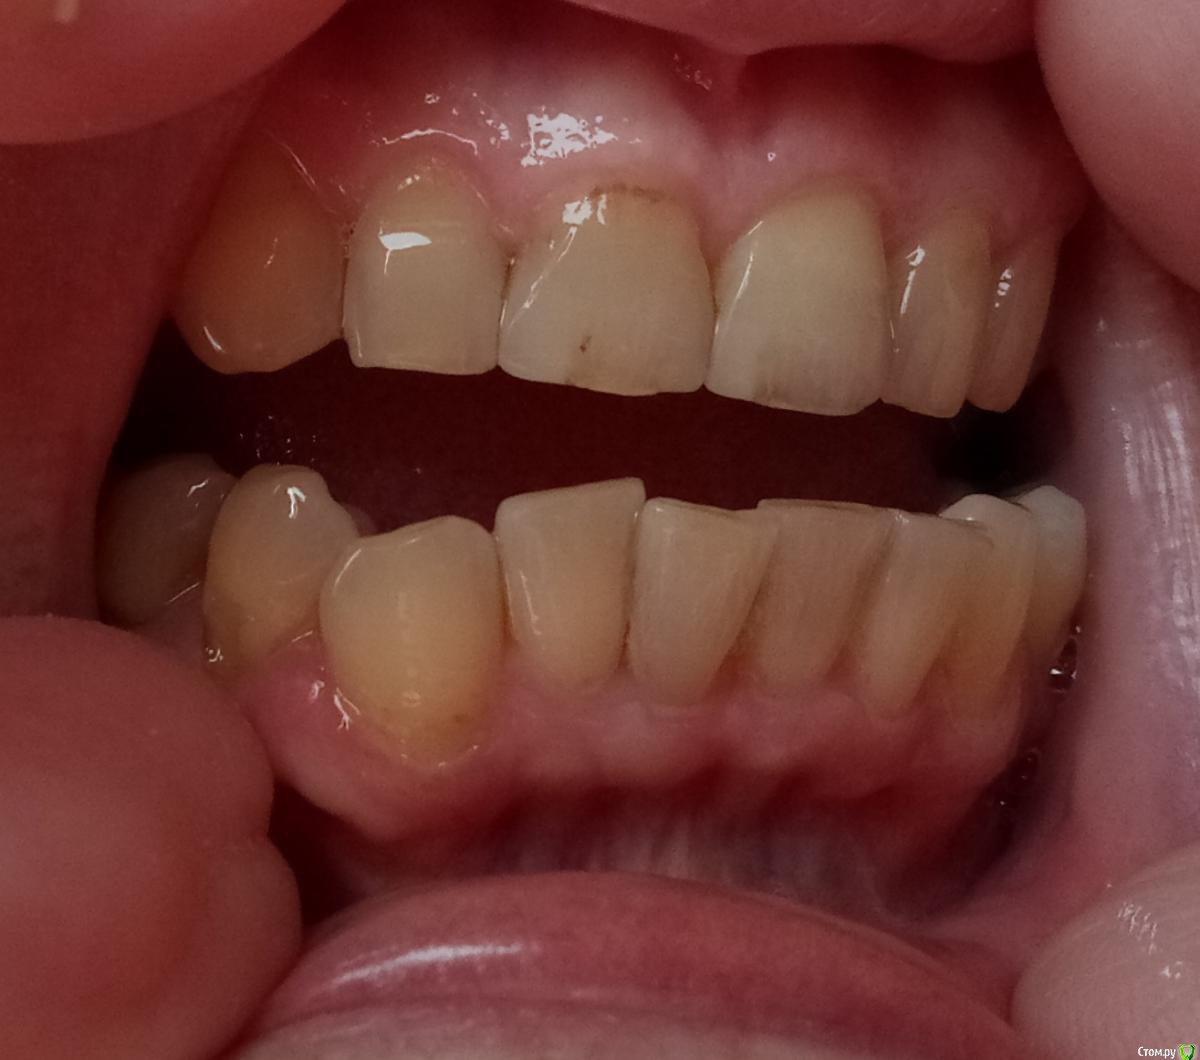

NaMe Опубликовано 13 февраля, 2020 Автор Поделиться Опубликовано 13 февраля, 2020 Добавляю фото. Надеюсь, что оно хоть в какой-то степени информативное. Ссылка на комментарий

red_butler Опубликовано 13 февраля, 2020 Поделиться Опубликовано 13 февраля, 2020 Добавляю фото. Надеюсь, что оно хоть в какой-то степени информативное.нужно наладить индивидуальную гигиену, в идеале кроме ирригатора использовать электрическую зубную щетку. И продолжить сотрудничество с пародонтологом. Ссылка на комментарий

NaMe Опубликовано 13 февраля, 2020 Автор Поделиться Опубликовано 13 февраля, 2020 нужно наладить индивидуальную гигиену, в идеале кроме ирригатора использовать электрическую зубную щетку. И продолжить сотрудничество с пародонтологом.Даже не знаю, как ее еще наладить. Об электрической щетке почитаю. Это единственное, чего я еще не применяла. И есть одно сомнение. В свое время из-за повышенной чувствительности эмали мне рекомендовали мягкую щетку. А мне кажется, что она очень плохо справляется со своими задачами. Может, еще и в этом проблема? Ссылка на комментарий